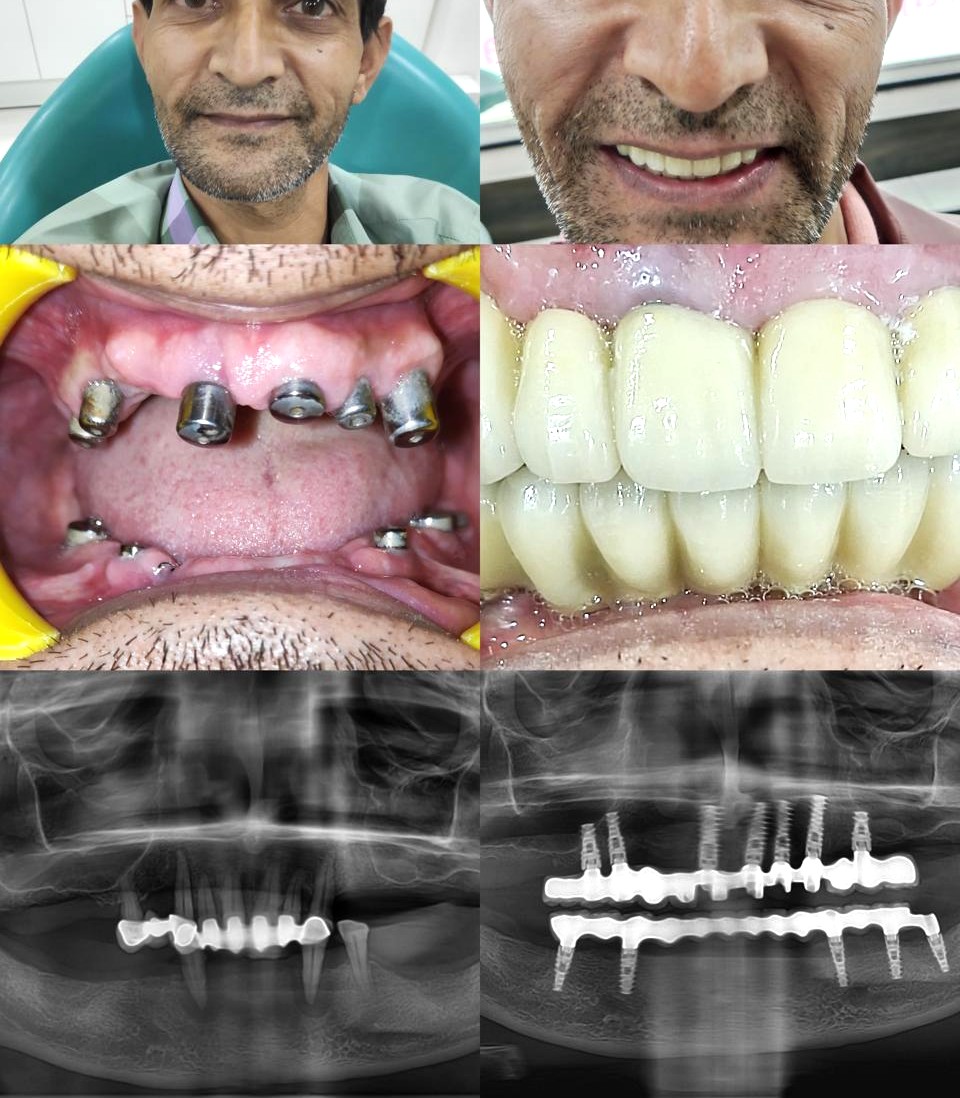

JP Dental Clinic is a leading dental clinic in Koramangala, Bangalore, providing comprehensive dental care with a focus on comfort, precision, and long-term oral health. Our experienced dentists offer advanced treatments including dental implants, root canal treatment, braces and aligners, veneers, teeth whitening, and pediatric dentistry.

Dr. Jaipal Reddy is an experienced and highly regarded dental surgeon and cosmetic dentist based in Koramangala, Bengaluru. He is the founder and lead dentist at JP Dental Clinic, a well-established dental practice known for comprehensive, patient-centric oral care. Dr. Reddy holds a Bachelor of Dental Surgery (BDS) degree from the Government Dental College and Research Institute, Bangalore, and brings over 25 years of clinical experience in general dentistry, endodontics, and cosmetic dental procedures.